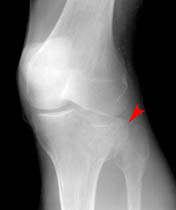

Lateral Tibial Plateau Fracture

• Also known as "fender" or "bumper" fractures, tibial plateau fractures most often are the result of a moving vehicle striking the knee.

• Plateau fractures (medial and lateral) are the most common fracture sustained at the proximal tibia.

• When depression is not present, fracture may be difficult to recognize with standard radiographic exam. Alternative views and/or CT may be required for diagnosis.